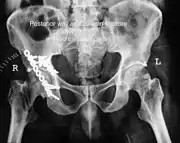

Posterior wallThis is the most common variety of acetabular fracture. It typically occurs due to dashboard injury; when a person travelling in a vehicle involved in a head-on collision, the force applied over the flexed knee travels along the femur bone to the head of the femur, breaking the posterior wall of the acetabulum. The head of the femur is dislocated outside the joint. T shapeWhen a transverse fracture also had a vertical fracture line, it is called a T shape fracture. Here the innominate bone is broken in such a way that all three parts of it, the ilium, the ischium and the pubis are separated from one another. This is a three part fracture. Though both columns are broken, the weight bearing dome is still attached to the main part of the ilium and hence it is not a true fracture of both columns.

This fracture may be associated with a fracture through the posterior wall as well, making it more complex. This fracture typically occurs when the injuring force is applied from the side, against the greater trochanter of the femur, as in a fall on the side or being hit on the side. This force may be combined with dashboard injury as well. The fracture is best seen in anteroposterior view and iliac and obturator oblique views.